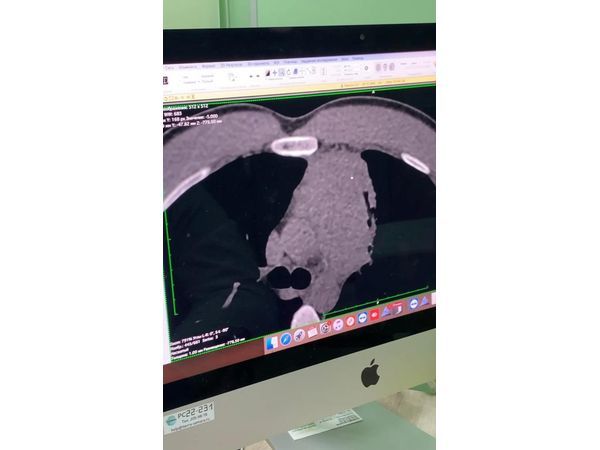

- компьютерную топографию органов грудной клетки (КТ ОГК) — обнаружено объёмное образование средостения;

Лимфома Ходжкина.